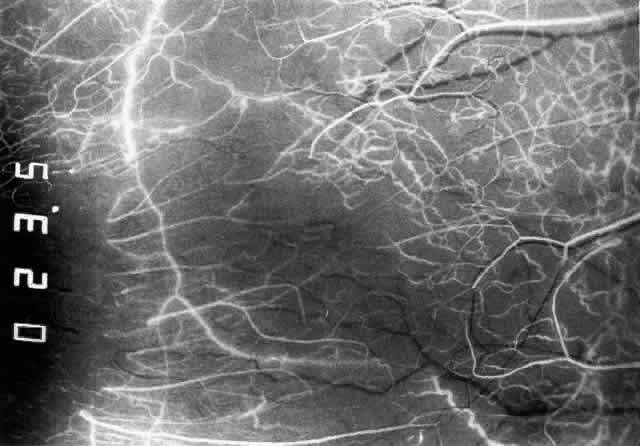

The anterior ciliary arteries run radially toward the limbus within Tenon's capsule, giving few, if any, branches until they reach the anterior part of the globe. Their positions are very variable, and they do not always follow the rectus muscles. They bifurcate 2 to 5 mm behind the limbus, and each division runs forward and circumferentially to anastomose with a branch from an adjacent artery. This results in an anterior episcleral arterial circle (Figs. 3 through 5). The divisions of the anterior ciliary arteries are typically superficial at their origins but run deeper at their anastomoses. They occasionally dip too deep to be seen in fluorescein angiograms (Fig. 6).

Fig. 3. Normal superior anterior segment angiography in a 35-year-old man. The main anterior ciliary arteries have filled, branching at or adjacent to the limbus to fill the limbal arcade, the recurrent branches of which are passing backward to fill the episcleral and conjunctival vessels. The episcleral circle here is superficial, and the anastomotic vessels are readily visible. There is a close resemblance to the vascular pattern in Figure 1, including the penetrating vessels adjacent to the limbus.

Fig. 4. Normal temporal angiogram of a 32-year-old woman. Fluorescein first enters the anterior ciliary artery above (as in Figure 3), filling the limbal arcade, and then dips deep into the sclera adjacent to the limbus; it can just be distinguished in the deep scleral tissue adjacent to the limbus. The posterior tarsal circulation can be seen filling at the same stage.

Fig. 5. Normal temporal angiogram in the same 32-year-old woman as in Figure 3 two seconds later. The superficial episcleral vessels are filling from a superficial branch of the anterior ciliary artery; the deep circle is now difficult to define but can be seen contributing to the iris vascular filling. The limbal arcade and conjunctiva near the limbus are filled from the superficial branches. Both the episcleral plexus and the conjunctival plexuses perfuse late, about 3 mm from the limbus. This watershed zone is important in the etiology of scleral disease.

Fig. 6. Normal left temporal angiogram of a 33-year-old man. In this angiogram the anterior conjunctival vessels and episcleral vessels are derived from the main ciliary artery trunk at the limbus, filling simultaneously with the iris vessels at a very early stage of the angiogram.

From the anterior episcleral arterial circle, four distinct circulations are supplied: episcleral, anterior conjunctival, limbal, and iris.

Episcleral Circulation

Immediately after their origin by bifurcation of the anterior ciliary arteries, the contributions to the anterior episcleral circle divide again to give recurrent branches that run posteriorly and subdivide to form a netlike episcleral plexus (see Fig. 5; Fig.7). The variability of the positioning of the anterior ciliary arteries inevitably leaves large areas of episclera far from such an arterial supply (see Figs. 4, 6, and 7). These areas receive other posterior branches from the episcleral circle. Where the circle runs deep within the sclera, such branches appear as isolated perforating vessels (see Fig. 6). They fill very shortly after the episcleral circle, and they also divide repeatedly as they run posteriorly.

Fig. 7. Normal left temporal angiogram of the same 33-year-old man as in Figure 6 eight seconds later. The episcleral circulation is being filled from a perforating vessel near the limbus derived from the deep circle. These eventually anastomose with vessels posteriorly and above. The conjunctival circulation is also late in filling. The main trunk of the artery can no longer be distinguished because of superficial leakage of dye.